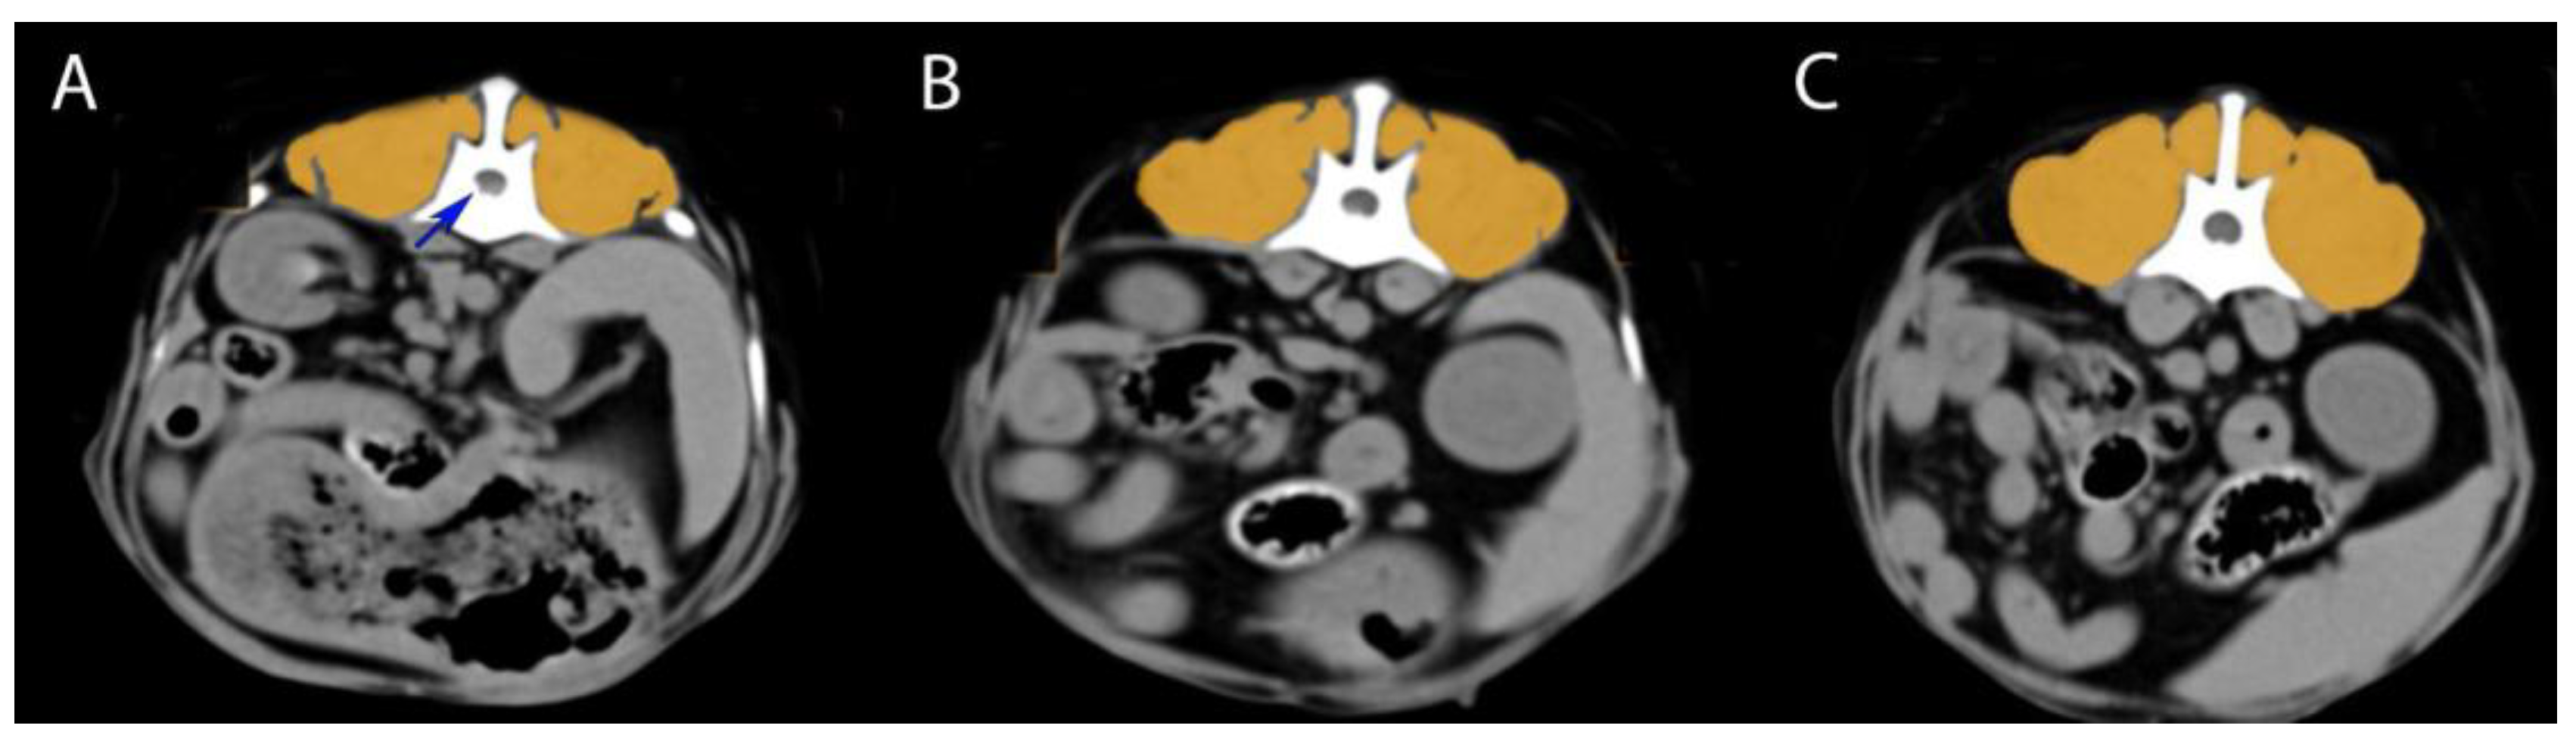

Epaxial muscle groups (multifidus, longissimus, iliocostalis muscles) were identified bilaterally on each image. Using RadiAnt DICOM viewer 2025.1 (Poznań, Poland), Horos DICOM viewer (Annapolis, MD, USA), the muscle area was manually outlined through freehand tracing, excluding adjacent fat or tissues. The software calculated the mean muscle attenuation (HU), standard deviation, and cross-sectional area. Six HU readings per dog were collected; this process was performed bilaterally on each image (left and right sides were measured separately) to assess any asymmetry. In total, six HU readings were obtained per dog (left and right at M1, M2, and M3). All measurements were performed by a single trained observer to ensure consistency. Figure 1 illustrates the measurement technique on a representative case.

Figure 1. Measurement technique on a representative case—CT transverse images from a Bichon Frisé with an acute L1–L2 disc herniation (blue arrow indicates herniated disc material compressing the spinal cord). The epaxial muscles are outlined in orange. (A) Measurement at the herniation level (L1–L2); (B) measurement one segment cranial to the herniation (T13–L1 level); (C) measurement one segment caudal to the herniation (L2–L3 level).